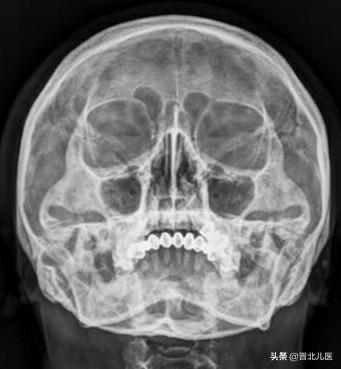

瓦氏位:被检者俯卧与摄影床上,正中矢状面垂直于床面。

中心线:经鼻根部垂直射入。

瓦氏位主要是用于筛窦病变、上颌窦病变。

瓦氏位怎么摆位置,瓦氏位柯氏位梅氏位斯氏位(常见头颅X片)